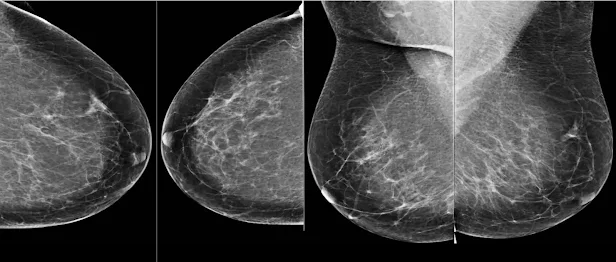

Маммограмм бүр дөрвөн зурагтай байдаг - хөх тус бүрээс хоёр өөр өнцгөөс.